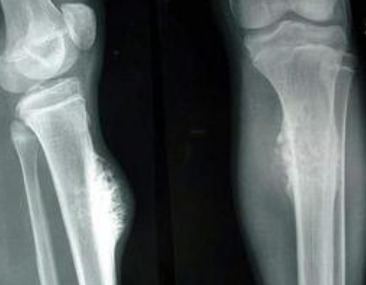

2021年,我被诊断出患有骨癌。那段时间,我的世界仿佛崩塌了。原本以为这只是生活中的一个小插曲,没想到却成了我人生中最艰难的一段旅程。为了治疗,我接受了长达一年多的化疗,总共进行了17次。每一次化疗都让我感到极度疲惫,身体的每一个细胞都在抗议,但我知道,只有坚持下去,才能有机会战胜病魔。

就在我以为一切都在慢慢好转的时候,命运再次给了我沉重一击。2023年底,我在一次例行检查中被确诊为急性白血病。那一刻,我几乎崩溃。骨癌已经让我身心俱疲,而白血病更是让人闻风丧胆的疾病。但我没有放弃,家人和朋友的支持给了我巨大的力量。